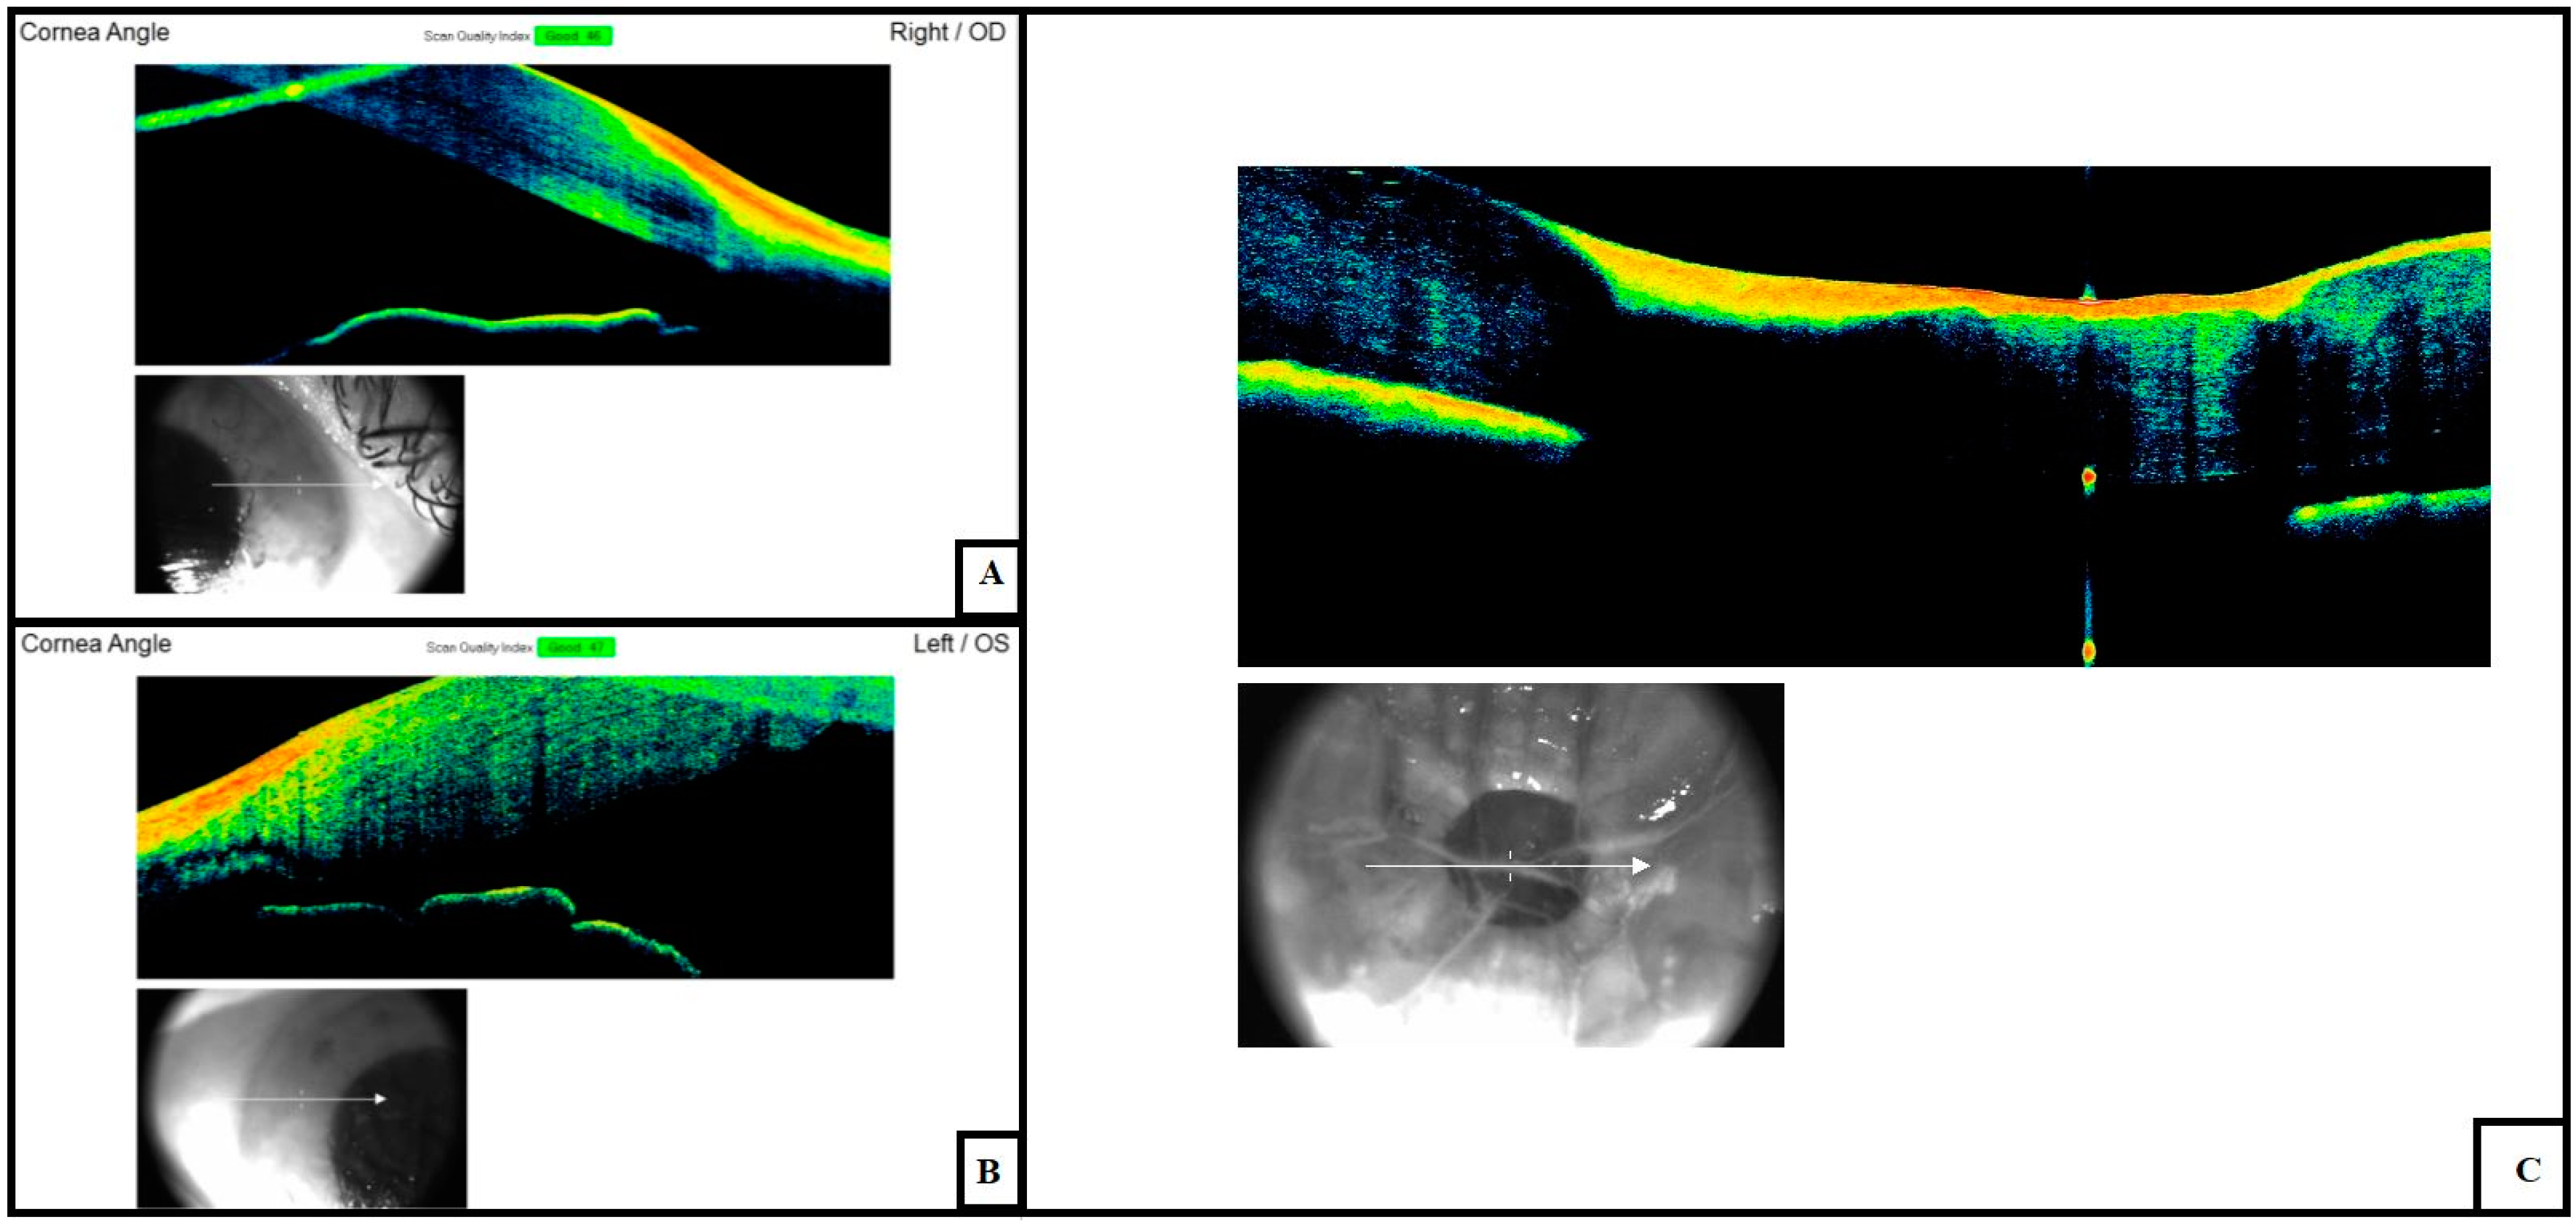

3.1. Cornea and Anterior Chamber

3.2. Sclera

3.4. Retina